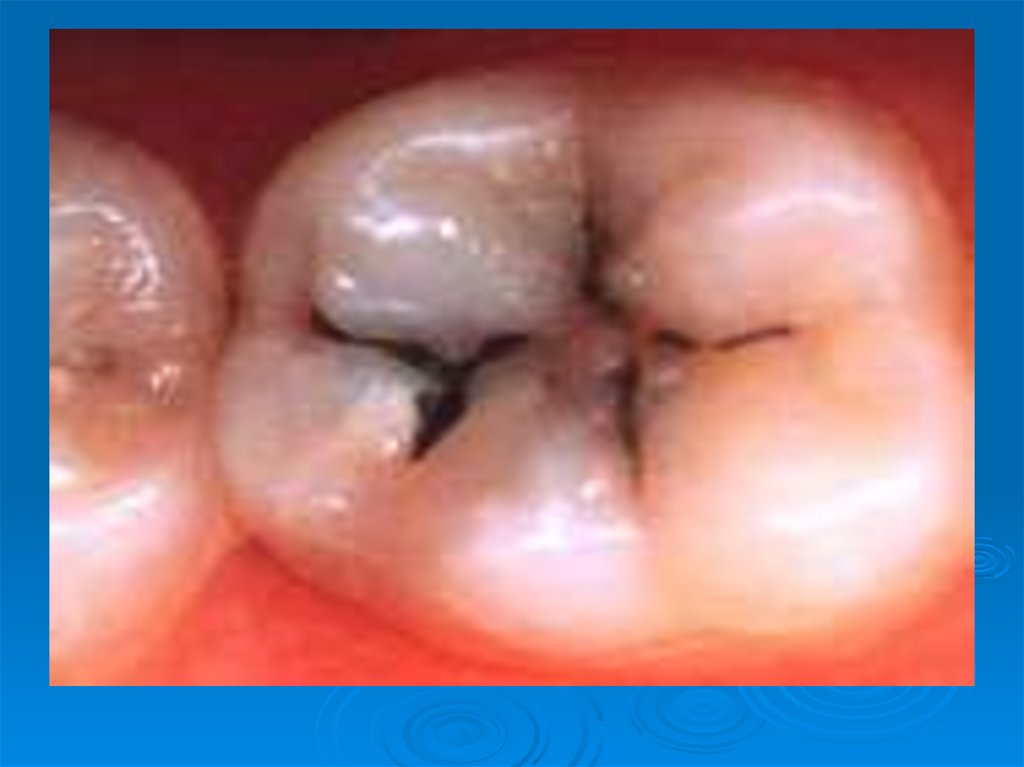

Кариес зубов – патологический процесс, проявляющийся после прорезывания зубов, при котором происходят деминерализация и

Современная концепция этиологии кариеса

6. Кариес зубов – патологический процесс, проявляющийся после прорезывания зубов, при котором происходят деминерализация и

размягчение твердых тканей зуба с

последующим образованием

дефекта в виде полости.